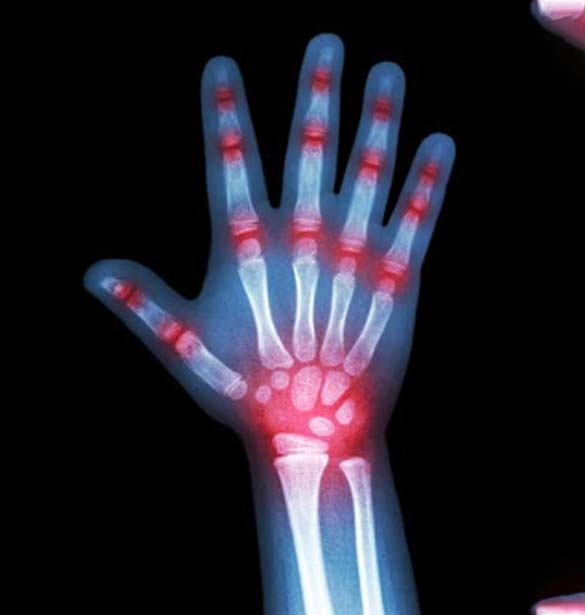

Rheumatoid arthritis of the hands, Xray Stock Image C039/1640 How Long Does Hand Arthritis Last Soak your hand in a tub of warm water for 20 minutes. Learn more about the causes, risk factors, symptoms, diagnosis,. how long does it take to recover from hand surgery? early arthritis in the fingers can cause dull, achy pain, stiffness, swelling, and weakness in the joints. In general, hand arthritis can last for several years or. How Long Does Hand Arthritis Last.